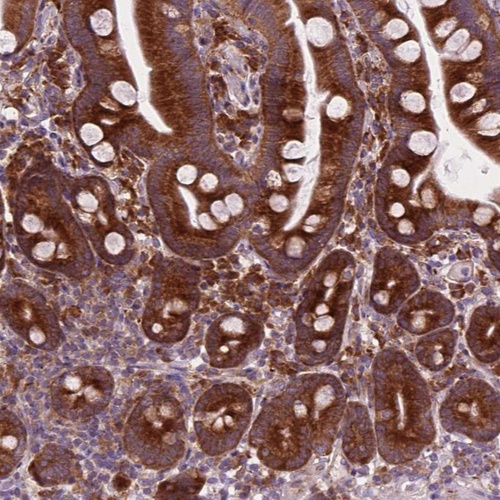

Immunohistochemical staining of human small intestine shows strong granular cytoplasmic positivity in glandular cells.